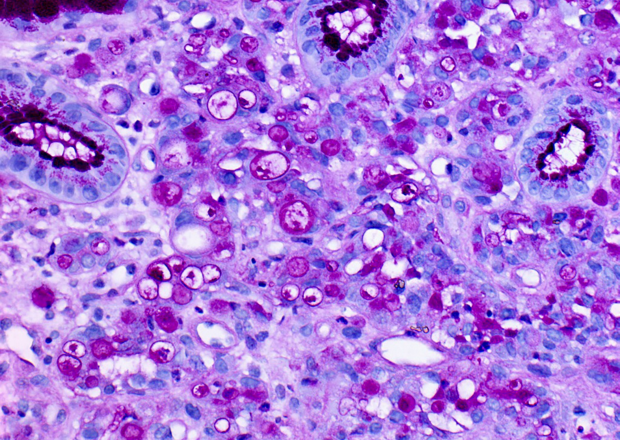

Dr Carmen van Dooijeweert’s PhD thesis is a great example of how a large collection of archived pathology records can be used for research. Van Dooijeweert’s research, which focused on improving the assessment of biomarkers for breast cancer, was largely based on protocolised pathology reports from the national Palga database.